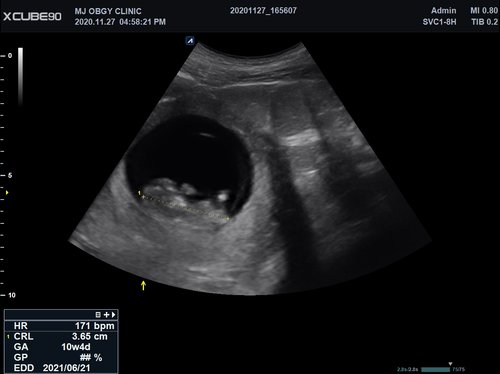

Volumen Konvex-Sonden

• SVC1-8H (1-8 MHz) für Ultraschalluntersuchungen in Bereichen Abdomen, Geburtshilfe, Gynäkologie, Urologie, Pädiatrie, EM